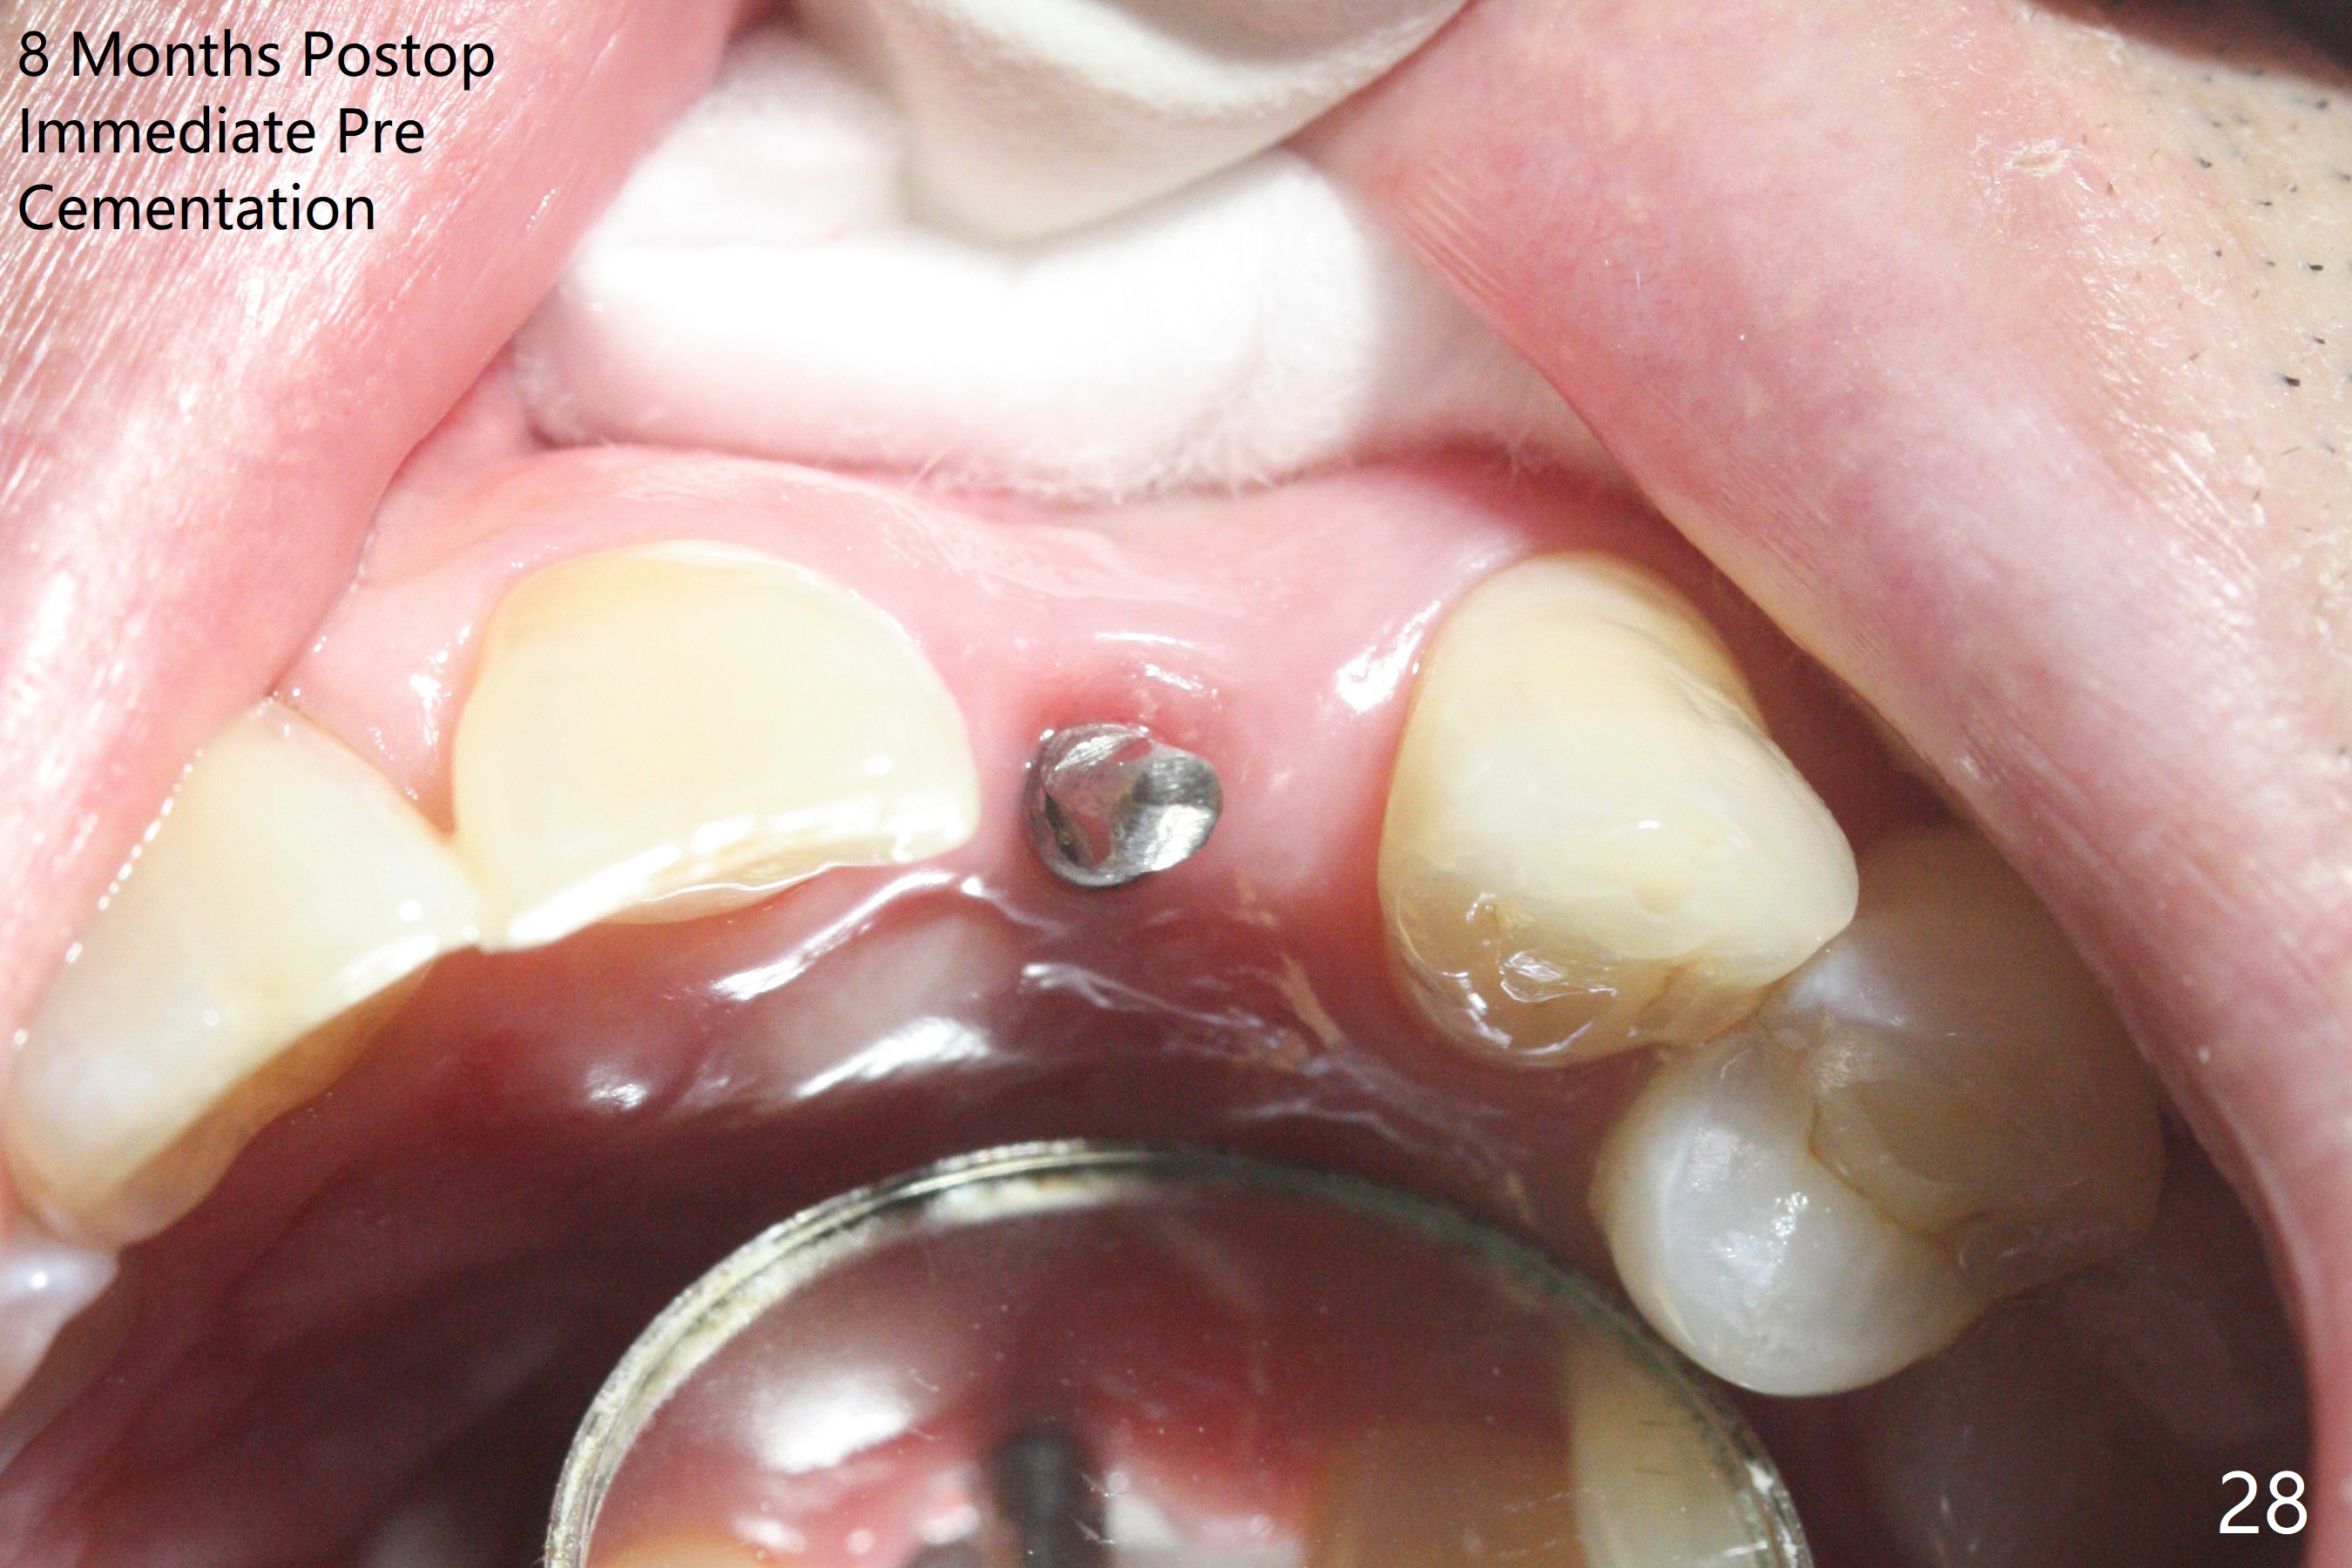

病人回来带来瘘道(图一),不过不会增加难度,病牙去除,它便自动消失。尽管颊侧骨壁完全失去,颊侧牙龈仍丰满(图二),为什么呢?第一,因为粗大牙根存在,第二两旁牙齿,牙槽骨撑着帐篷(侧切牙颊侧牙龈),第三,牙冠。为了防止术后牙龈塌陷,尽量不切开,即刻放置植体(牙根);由于前牙缘故,这次植体不能很大,所以植骨必须过度(over grafting),最后即刻制作临时牙冠,撑住牙龈。这就是所谓每个人进入角色。这个牙根有一种先天性畸形:dens in dent (图三(腭侧观):箭头)。尽管腭侧牙根畸形,腭侧骨壁吸收临床上并不严重,所以钻洞仍偏腭侧。当预定最后钻头还在钻洞时,填入大量粘性骨块(图四:*),细长植体还没有完全卡入鼻底(图五),最后好像可以(图六,七)。植体,骨粉入位(图八),最后临时牙冠出场(图九)。尽管植体小,术后一周临时牙冠仍然可以维持牙龈原有形状(emergency profile,图十:箭头(*:树脂强化牙冠固定))。图十一以不同角度显示瘘道缩小。术后三周取出有些松动的临时牙冠,骨粉虽然还没有被肉芽组织整合,但是显得正常,周围牙龈健康(图十二)。术后4个月牙龈形态正常(图十三),没有触痛;颊侧骨板轻度凹陷(图十四);骨粉仍在原位(图十五)。术后7个月骨粉仍在原位(图十五,十六,但是冠部密度减低(可能骨粉流失,需要牙周或者树脂敷料保护)),没有螺纹暴露。但是牙冠边缘暴露,说明牙龈收缩(图十七,与图十三对比),颊侧骨板仍塌陷(图十八)。插入龈线取得多个目的:修整基台边缘,取模,颊侧牙龈推向颊侧,有利于即将衬里牙冠龈缘进入龈下(图十九)。取模后牙冠边缘(图二十:<)衬里,然后修整,变窄,以便插入龈下,促进颊侧牙龈下降(图二十一,二十二)。术后8个月牙冠粘固前牙龈健康(图二十七,八),牙冠(图二十九)固位后,病人满意(图三十),咬合调整(图三十一),注意腭侧粘固粉流出通道(<)。